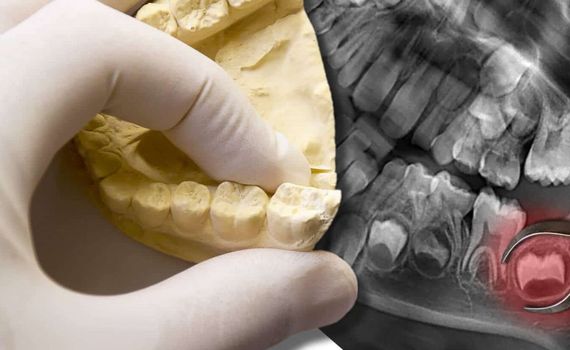

Wurzelspitzenresektion (WSR)

Bei einer Wurzelspitzenresektion handelt es sich um einen chirurgischen Eingriff, der durchgeführt wird, wenn eine Entzündung oder Infektion an der Wurzelspitze eines Zahnes nicht auf herkömmliche Weise behandelt werden kann. Dabei wird die entzündete oder infizierte Wurzelspitze entfernt und der Wurzelkanal danach versiegelt, um die Entzündung zu beseitigen und die Heilung zu fördern.

Weisheitszähne

Die Weisheitszähne kommen etwa zwischen dem 18. und 30. Lebensjahr durch. Aufgrund evolutionärer Veränderungen haben sie im mittlerweile „zu engen Kiefer“ jedoch oft keinen Platz, so dass sie gar nicht oder nur unvollständig durchbrechen. Eine Entfernung ist dann sinnvoll, um einem Engstand der übrigen Zähne bzw. Zahnfleischentzündungen und Karies an Weisheits- oder Nachbarzähnen zu vermeiden.